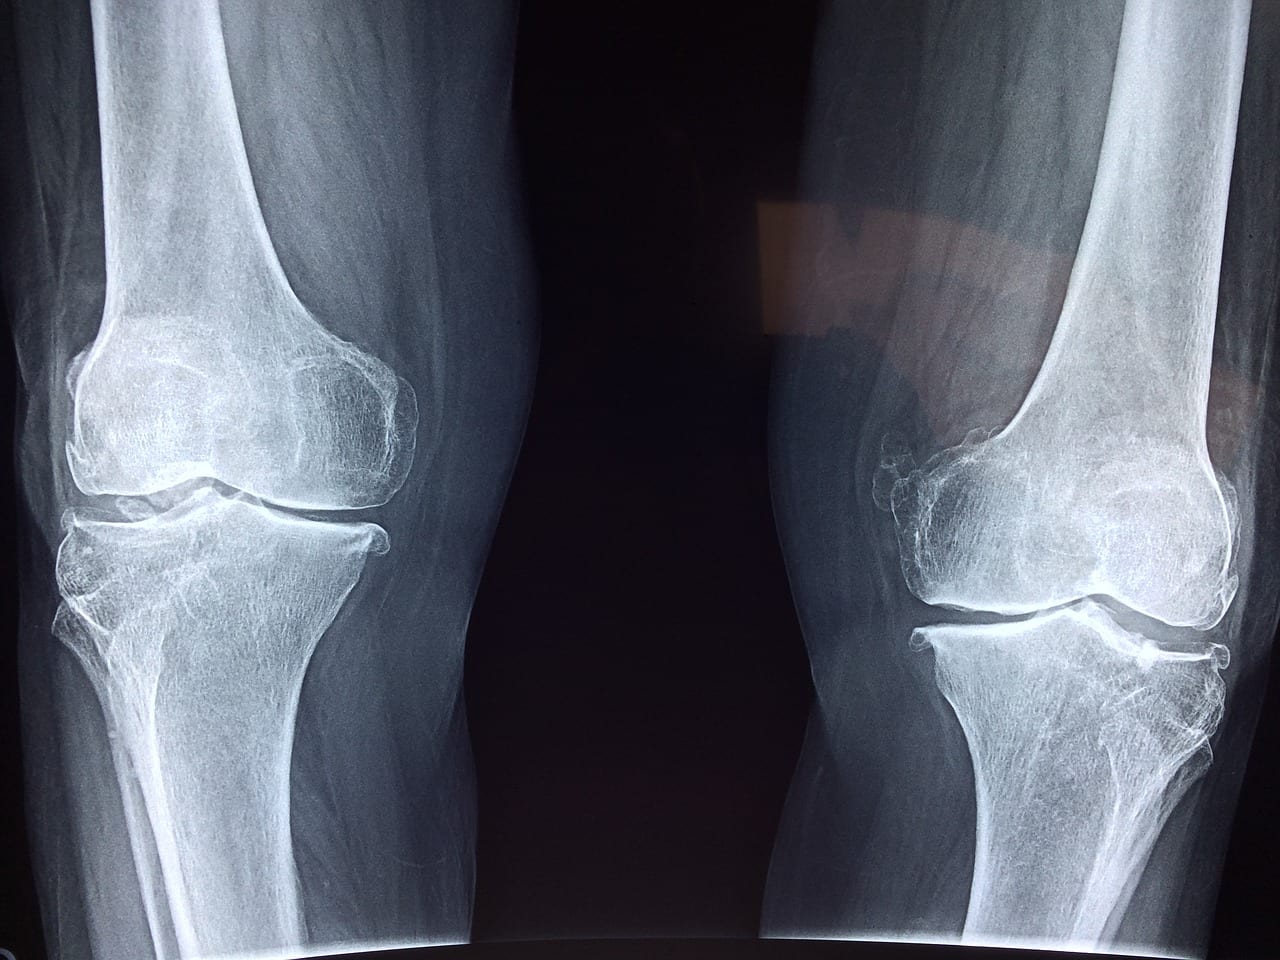

As you age the ligaments that maintain the stability of the joints lose their elasticity. Salat helps to keep these ligaments limber and stretched out. Especially in knees and ankles and feet.

Salat helps the knee joints in particular. It keeps them in good motion and the ligaments stretched out. It also helps strengthen the quadriceps muscle which is the biggest muscle that keeps your knee straight and stable.

The knees do get some wear and tear and arthritis that is consistent with age. However an un-injured knee remains pretty flexible. Usually sports injuries to the knees or knee that have had surgery end up having more arthritis and stiffness.

Women are more prone to get arthritis in knees than men. This is related to carrying increased load during pregnancies. In the walking each leg and knee carries 2 ½ times the body weight in the stance phase.

Men who are overweight tend to get more arthritis in the knees. Arthritis is function related. Use causes wear and tear and thus arthritis. The knees get it more because of weight issues. The first joint to get arthritis is the basal joint of thumb. Women get more because of kitchen work and house work etc.

In our village culture and Japanese culture because they sit on the floor with their knees flexed and they still tend to use the old squatting down toilets the knees are more flexible.